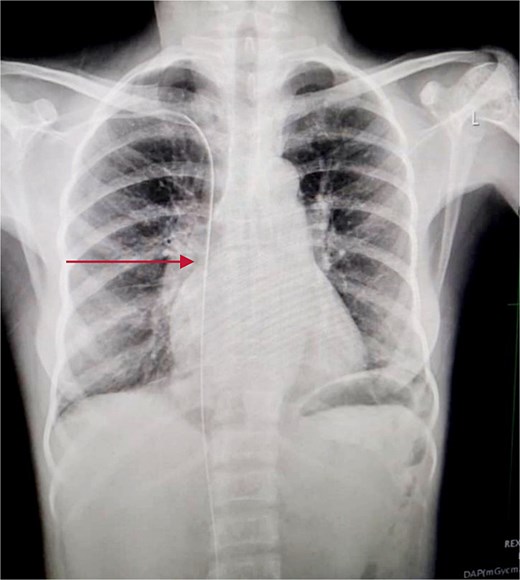

Chest and abdominal X-rays revealed the guide wire extending from the right subclavian vein through the superior vena cava (SVC), right atrium, and inferior vena cava (IVC) to the proximal right femoral vein (Figs 5 and 6).

Chest X-ray showing guide wire extending from the right subclavian vein to the SVC and via the right atrium to the IVC.